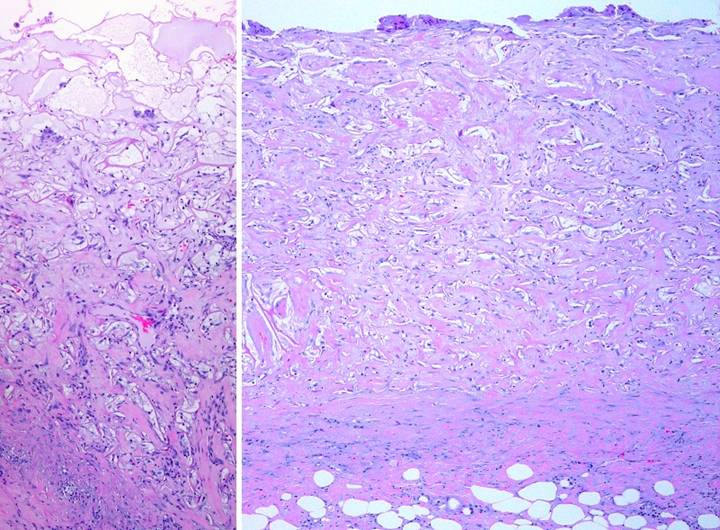

Case Study 12,  Location, leg.   A 77 year old woman had a 40 year history of continuous leg ulceration and progressive systemic illness.  In spite of classic symptoms of Sjögren’s disease, the diagnosis was missed countless times.  When seen in consultation, the diagnosis was made, anti-inflammatory and antimetabolic treatments were started, and the patient’s general health status improved substantially.  (Figures 12a,b)  The leg ulcers are shown just prior to excision.  Proper excision means thorough fasciectomy, removing all pathological tissues, including the fibrotic, ulcerated, and inflamed sural fascia.  This means that muscles, tendons, retinacular ligaments and other structures will all be exposed when excision is complete.  Skin grafts will not cover these structures, and even if they could in principle, here they would be at risk for recurrent pathological lysis and ulceration.  (Figures 12c,d)  The legs and ankles are shown one week after excision and Integra.  Note the wrinkling in the Integra, a common occurrence due to control of  inflammation and edema, thereby decreasing limb volume and surface.  All care was outpatient.  (Figures 12e,f)  The legs healed and have stayed stable, shown here two years later.  Note the bandaging imprints, attesting to the patient’s diligent efforts to control edema and care for her skin.  Consistent rheumatology management has kept the patient healthy, and lifestyle has been restored.  (Figure 12g)  A close-up view shows the quality and texture of the regenerated material and how comparable it is to normal skin.

Figure 12  a, b (left column), c, d (middle column), e, f (right column), g (bottom)